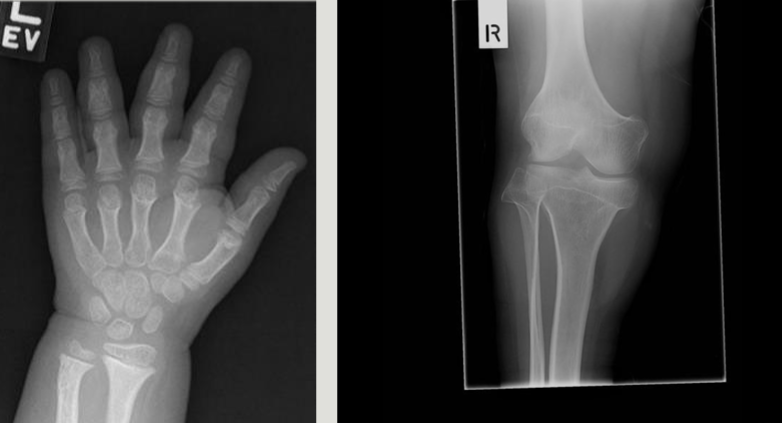

Classification - Delayed/Advanced Bone Age

Reason for Radiographs - Delayed/Advanced Bone Age

assessment of growth and evaluation of endocrine disorders

used to investigate: short/tall stature, early/late puberty, to predict height

Radiographic Appearance - Delayed/Advanced Bone Age

taller/shorted than average

carpal ossification ages

cap 1-3 months

ham 2-4 months

tri 2-3 years

lunate 2-4 years

scap/trap/trap - 4-6 years

pisi - 8-12 years